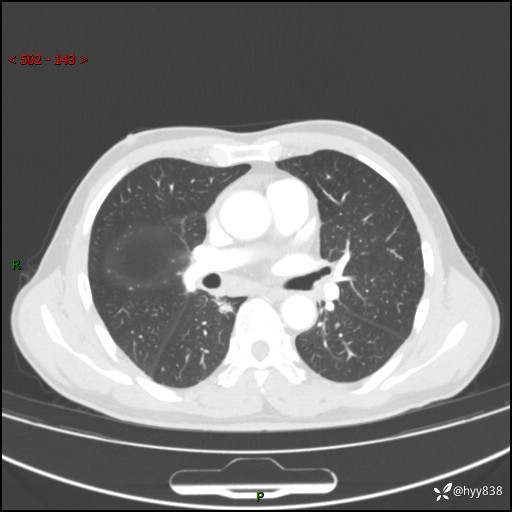

69岁/男,发现肺部病变6天。该有的征象都有,肉芽肿 VS 肿瘤,一念之间---(有结果)

主诉:发现肺部病变6天。

现病史:患者6天前于我院泌尿外科住院,住院期间行胸部CT检查,提示“肺部病变”,患者无畏寒、发热、盗汗、咳嗽、咳痰、咯血、胸痛、呼吸困难,无反酸、腹痛、腹泻、头痛、头晕等不适。未予特殊处理,现为进一步诊治,门诊以“肺肿物”收入我科。 患者本次起病以来,精神食欲尚可,大小便正常,体力及体重无明显变化。

胸部CT平扫+增强